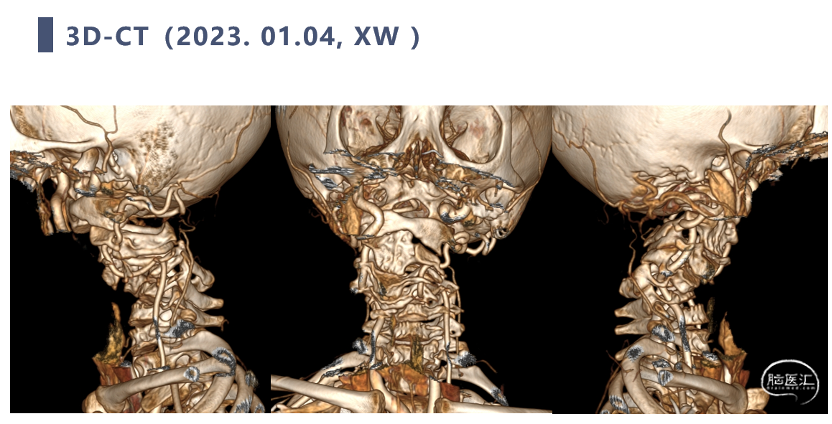

CT

CT显示颈椎椎体最大深度只有8mm,枢椎椎弓根直径3.2mm

双向牵引后,患者后方小关节仍存在一定绞锁,首先行后路手术,充分松解后方绞锁的关节突。再行前路手术,矫正后凸畸形,前路手术时因患者骨量极少,单纯前路螺钉复位力量弱,借助提拉工具完成良好复位。最后翻身行后路手术完成C2-7后路固定,因患者多数侧块发育异常,双侧C4-5无法置钉,应用椎板钩固定,双侧C2椎弓根直径只有3.2mm,但成功置入了两颗3.5mm螺钉。